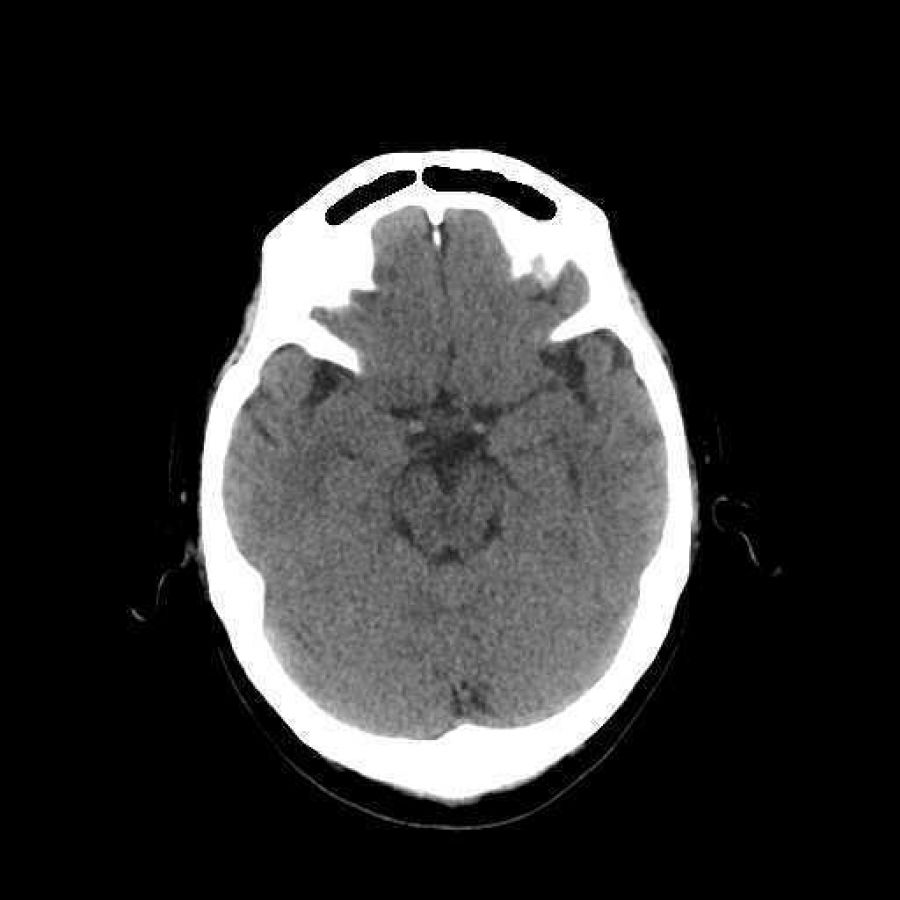

El Dr. López Tapia comentó que, lamentablemente, hoy en día 70% de quienes presentan alta sospecha de infarto cerebral llegan al hospital tarde y por sus propios medios y, ya estando ahí, resulta que el centro de salud no cuenta con un tomógrafo para el diagnóstico preciso, con terapia de reperfusión ni personal capacitado para suministrarla. “De modo que por cada minuto que pasa, el cerebro pierde cientos de neuronas, dejando al paciente con secuelas graves que se traducen en pérdida de la movilidad, visión, lenguaje y disminución de la capacidad intelectual[4]”.

Por su parte, el Dr. Christian Valencia Pineda, representante de la Iniciativa Angels en México, sostuvo que “a partir del trabajo conjunto la SMME, la AMEVASC y nosotros, hemos puesto en operación una estrategia con la cual detectamos la más grande red hospitalaria de instituciones pública y privadas en el país que cuentan con sala de emergencias, tomógrafos en funcionamiento, entrenamiento a médicos y personal de salud en la interpretación de estudios diagnósticos y la terapia de reperfusión para restablecer la circulación de la arteria ocluida en caso de infarto cerebral isquémico agudo. Hoy tenemos 81 hospitales y esperamos que para 2019 este número se eleve a 174”, agregó.